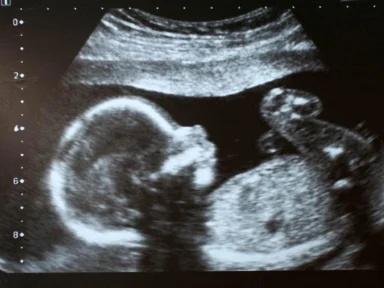

Selama ini, manusia bernapas menggunakan paru-paru. Hal ini memang benar, tetapi tidak berlaku bagi bayi yang masih berada dalam kandungan. Lantas, bagaimana cara bayi bernapas dalam kandungan? Simak informasi berikut untuk jawabannya.

Bagaimana cara bayi bernapas dalam kandungan?

Meski sudah memiliki paru-paru, organ yang membantu bayi bernapas di dalam kandungan adalah tali pusat yang terhubung dengan tubuh ibu hamil.

Bayi belajar bernapas sejak dalam kandungan

Bernapas adalah proses penting yang menunjang kehidupan manusia, termasuk bayi yang masih berada di dalam kandungan.

Meski pernapasan janin masih dibantu ibu hamil, sistem pernapasan mereka sebenarnya sudah dilatih sejak di dalam kandungan melalui tahapan-tahapan berikut.